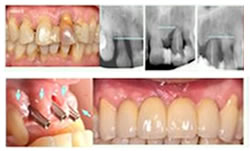

La reciente aparición de implantes de diseño anatómico evolucionado, sumada a los cambios biológicos propuestos que incluyen la colocación de los mismos a un mínimo torque para su fijación inicial, la no realización de incisiones ni de colgajos de tejidos blandos y la inexistente necesidad de realizar puntos de sutura, brindan una mejora notable en la respuesta posquirúrgica del paciente.

Por todo esto, hoy en día nos acercamos al ideal que desea todo paciente: extraer un diente y colocar en su sitio un implante que se comporte en el largo plazo como un diente natural, haciendo de este modo altamente predecibles los resultados clínicos obtenidos, y permitiendo dar respuestas a casos considerados hasta ahora como inviables, que se resolvían por medio de prótesis removibles que generaban gran disconformidad funcional, estética y psicológica en los pacientes.